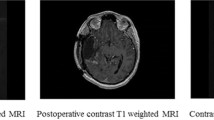

In the treatment of glioblastoma (GBM) the impact of radical tumor resection as first line therapy is beyond controversy. The significance of a second resection in case of tumor-recurrence remains unclear and is an issue of debate. Since GBMs always recur, it is important to determine whether or not patients will benefit from repeat surgery. We performed a retrospective analysis of our prospectively collected database and evaluated all re-resected patients with primary GBM who underwent second surgery during a 3 years period. All patients underwent early postoperative magnetic resonance imaging. We determined survival after re-resection with regard to possible prognostic factors using Kaplan–Meier estimates and Cox regression analyses. Forty patients were included in this study. Median age was 58 years and median KPS score was 80. Average tumor volume was 5.5 cm3. A radiologically confirmed complete resection was achieved in 29 patients (72.5 %). Median follow-up was 18.8 months, and median survival after re-resection was 13.5 months. Only complete removal of contrast enhancing tumor was significantly correlated with survival after re-resection according to multivariate analysis. There was a statistical trend for KPS score influencing survival. In contrast, time between first diagnosis and tumor-recurrence, tumor volume at recurrence, MGMT status and MSM score were not significantly correlated with survival after second surgery. In the event of tumor recurrence, patients in good clinical condition with recurrent GBM amenable to complete resection should thus not be withheld second surgery as a treatment option.